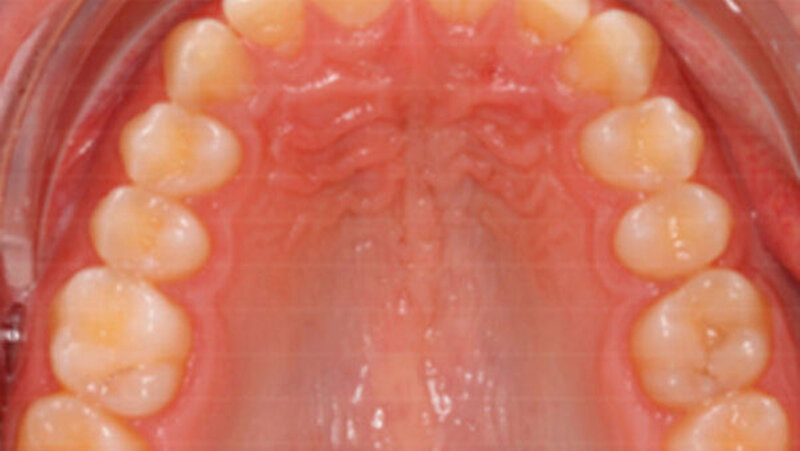

Initialer Befund nach Extraktion des Zahns 26

Abb. 1: Der dargestellte Patient stellte sich im Alter von 16:03 Jahren nach Überweisung durch die Klinik für MKG-Chirurgie zur Abklärung der Möglichkeit eines orthodontischen Lückenschlusses in regio 26 vor, da dieser Zahn nach erfolgloser endodontischer Therapie extrahiert werden musste. a und b: Frontal- und linke Seitenansicht auf die Zahnreihen mit frontalem Tiefbiss und Neutralverzahnung im Eckzahnbereich. c: Die Oberkiefer-Aufsicht zeigt, dass Zahn 27 bereits circa 1,5 mm spontan nach mesial migriert ist. d: Im Ausschnitt der Panoramaschichtaufnahme zeigt sich die Anlage von Zahn 28 mit erkennbarer physiologischer Kronenmorphologie. | Bernd G. Lapatki